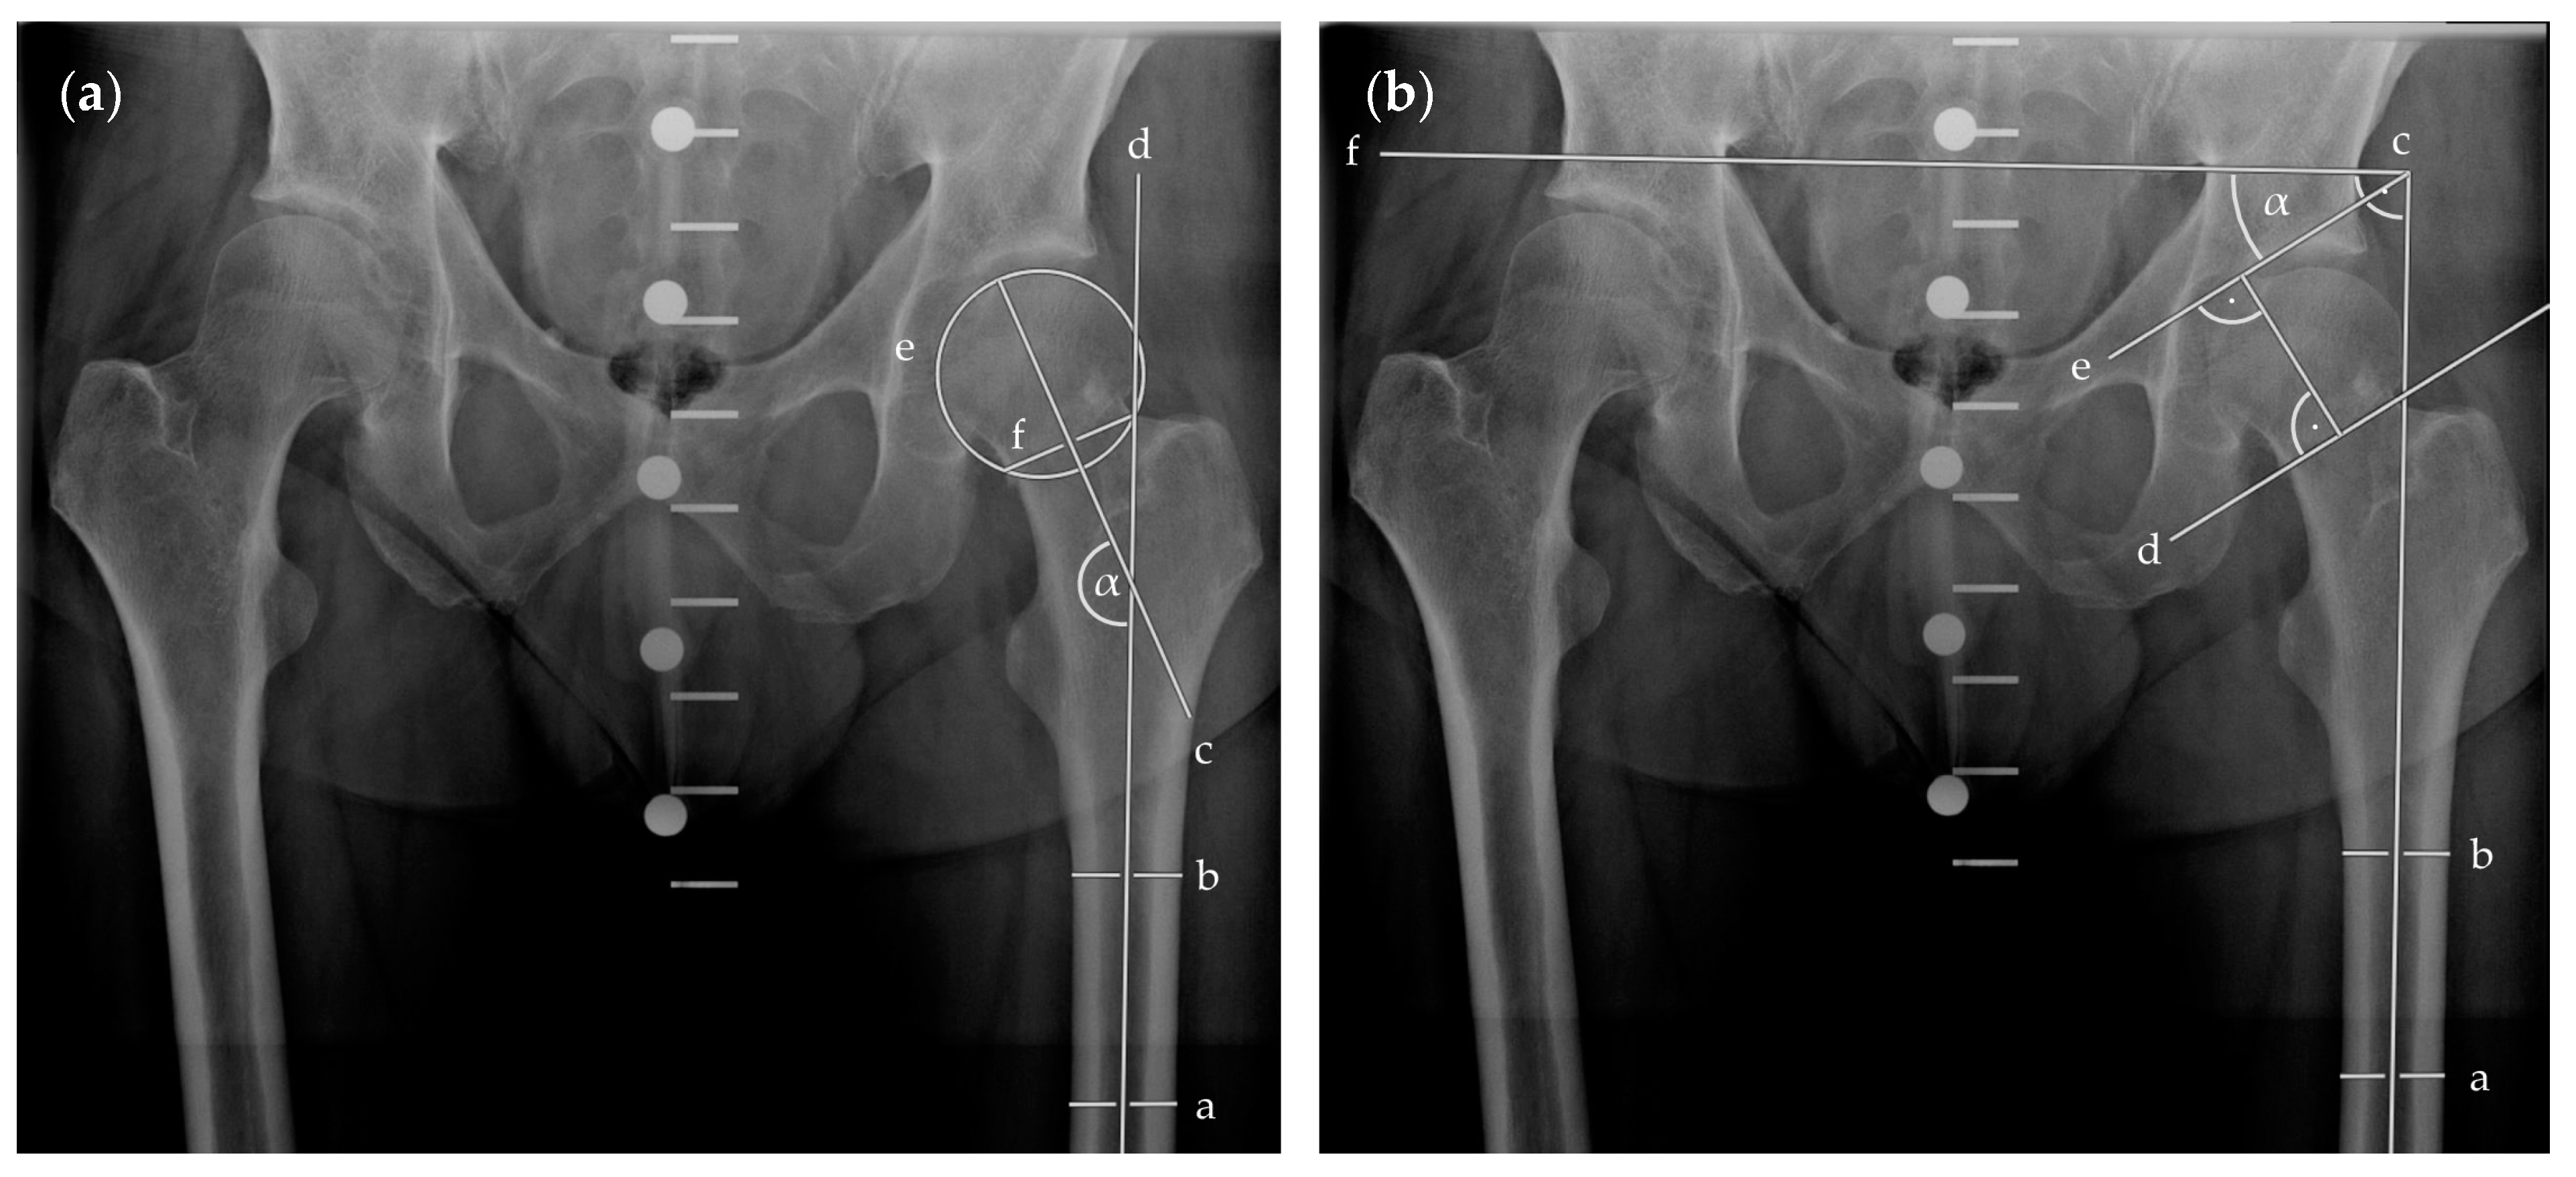

| Preoperative Pauwels angle (°) | 50.93 ± 14.07 | 47.66 ± 14.44 | p = 0.41 | |

| (95% CI 44.15–57.71) | (95% CI 38.49–56.83) | |||

| Postoperative Pauwels angle (°) | 46.74 ± 7.71 | 43.34 ± 7.93 | p = 0.22 | |

| (95% CI 43.03–50.46) | (95% CI 38.3–48.38) | |||

| Preoperative CCD angle (°) | 129.5 ± 16.21 | 130.8 ± 13.25 | p = 0.8 | |

| (95% CI 121.7–137.3) | (95% CI 122.4–139.2) | |||

| Postoperative CCD angle (°) | 135.9 ± 7.27 | 136 ± 5.24 | p = 0.85 | |

| (95% CI 132.4–139.4) | (95% CI 132.7–139.4) | |||

| Pauwels classification | Type I (% of group) | 1 (5.26%) | 1 (8.33%) | p = 0.72 * |

| Type II (% of group) | 10 (52.63%) | 7 (58.33%) | ||

| Type III (% of group) | 8 (42.11%) | 4 (33.33%) | ||

| Garden classification | Type I (% of group) | 2 (10.53%) | 1 (8.33%) | p = 0.45 ** |

| Type II (% of group) | 9 (47.37%) | 8 (66.67%) | ||

| Type III (% of group) | 4 (21.05%) | 2 (16.67%) | ||

| Type IV (% of group) | 4 (21.05%) | 1 (8.33%) | ||